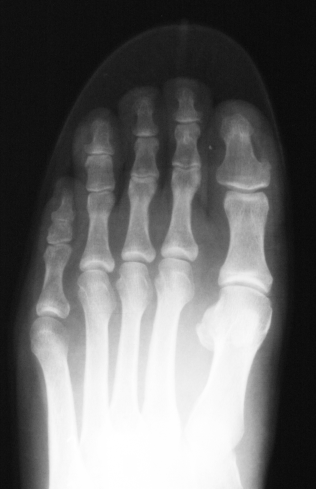

Und, auch das kannst du mir Glauben, nicht jede Frau wird durch ihre Absätze krank. Hallux valgus zum Beispiel entwickelt sich von Kindheit an. Ich kenne Mädchen um 12 Jahre, die haben bisher nur flache Schuhe getragen und sind bereits an der Grenze des operativen Eingriffes.

(Übrigens: Ich wundere mich immer, wenn ich schreckliche Hallux-Füße sehe; die armen Frauen können keine hohen Schuhe Tragen, haben sicherlich große Schmerzen bei Laufen, "versauen" sogar flache Schuhe/Stiefel mit grausigen Beulen. Und, es ist eine unkomplizierte, leichte Operation.